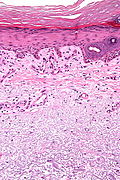

Micro

The sections show hair-bearing skin with abundant lymphocytes around and within the hair follicle wall.

The non-hair follicle epidermis has acanthosis, hypergranulosis and compact hyperkeratosis. There is no inflammatory cell infiltrate in the non-hair follicle epidermis or at the non-hair follicle interface.

There are no granulomas.